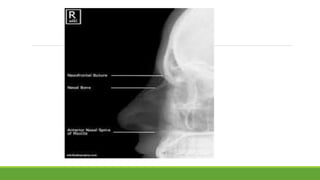

The document outlines the procedure for performing a nasal bone view X-ray, which is used to detect nasal bone fractures and foreign bodies. It provides details on patient positioning, X-ray beam direction, and image evaluation criteria, including specific exposure settings. Additionally, it references a positioning guide by Katharine 'Kitty' Clark.